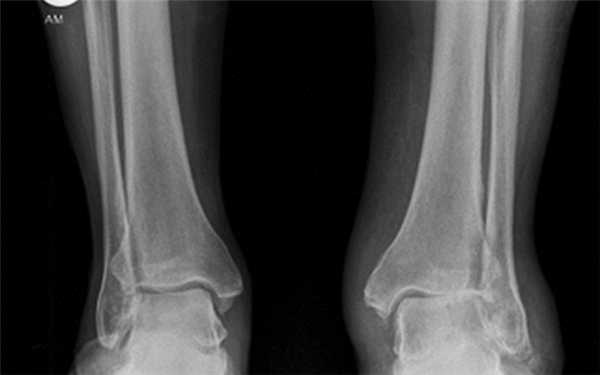

Рентгенологические стадии по Kellgren и Lawrence:

- 0 — полное отсутствие рентгенологических признаков;

- І — кистовидные изменения костной ткани, субхондральный линейный остеосклероз, краевые остеофиты небольшого размера;

- ІІ — сужение суставной щели, более выраженный остеосклероз;

- ІІІ — массивный субхондральный остеосклероз, сильное сужение суставной щели, остеофиты большого размера;

- ІV — массивные остеофиты, деформация эпифизов костей, практически полное отсутствие суставной щели.

Стадии остеоартроза голеностопного сустава

Классификация Н.С. Косинской:

- Начальная стадия. Характеризуется поражением только суставных хрящей. На рентгенограммах может визуализироваться незначительное сужение суставной щели, которое заметно лишь при сравнении с симметричным суставом.

- Стадия выраженных изменений. В дегенеративно-деструктивный процесс вовлекаются кости с развитием субхондрального остеосклероза. При рентгенографии выявляют краевые остеофиты и неравномерное сужение суставной щели как минимум на 50%.

- Стадия ярко выраженных изменений. Проявляется выраженным ограничением подвижности голеностопа. На рентгенограммах видны большие участки остеосклероза, массивные остеофиты, деформация костей и нарушение конгруэнтности суставных поверхностей.

В клинической практике в России и странах СНГ чаще всего используют классификацию Н.С. Косинской.

- Рентгенография. Информативна на поздних стадиях заболевания, но не всегда позволяет обнаружить ранние изменения. С помощью рентгенографии можно визуализировать субхондральный остеосклероз, остеофиты, костные деформации, сужение суставной щели.